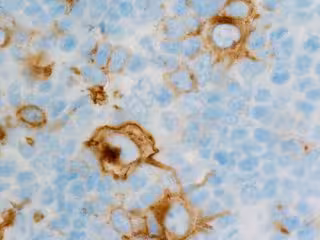

Linfoma de Hodking

FLIKR/CNICHOLSONPATH - Archivo